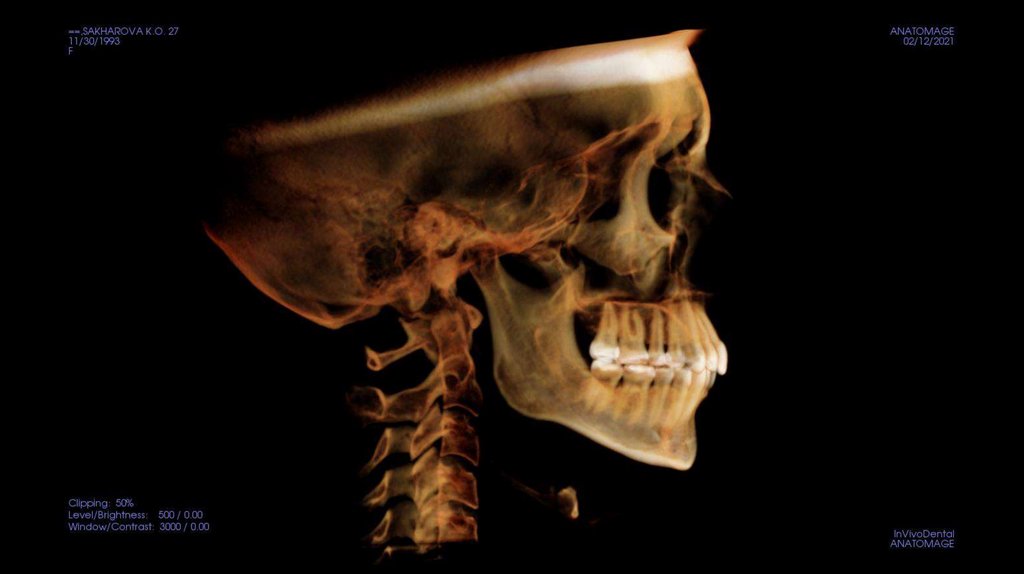

По рассчетам снимков:

• Ретрузия резцов верхней челюсти

• Компрессия головок суставов, особенно правого( началось

ремоделирование)

• Костная ассиметрия(10 мм)

• 2 класс

• 25, 46 зуб – нуждается в санации

• Требуется профессиональняа гигиена полости рта

• Клиновидные дефекты 43, 44

• 18, 28, 38, 48 отсутствуют.